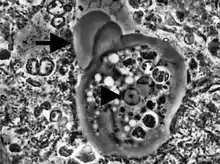

Entamoeba histolytica trophozoite

Entamoeba cells are small, with a single nucleus and typically a single lobose pseudopod taking the form of a clear anterior bulge. They have a simple life cycle. The trophozoite (feeding-dividing form) is approximately 10-20 μm in diameter and feeds primarily on bacteria. It divides by simple binary fission to form two smaller daughter cells. Almost all species form cysts, the stage involved in transmission (the exception is Entamoeba gingivalis). Depending on the species, these can have one, four or eight nuclei and are variable in size; these characteristics help in species identification.